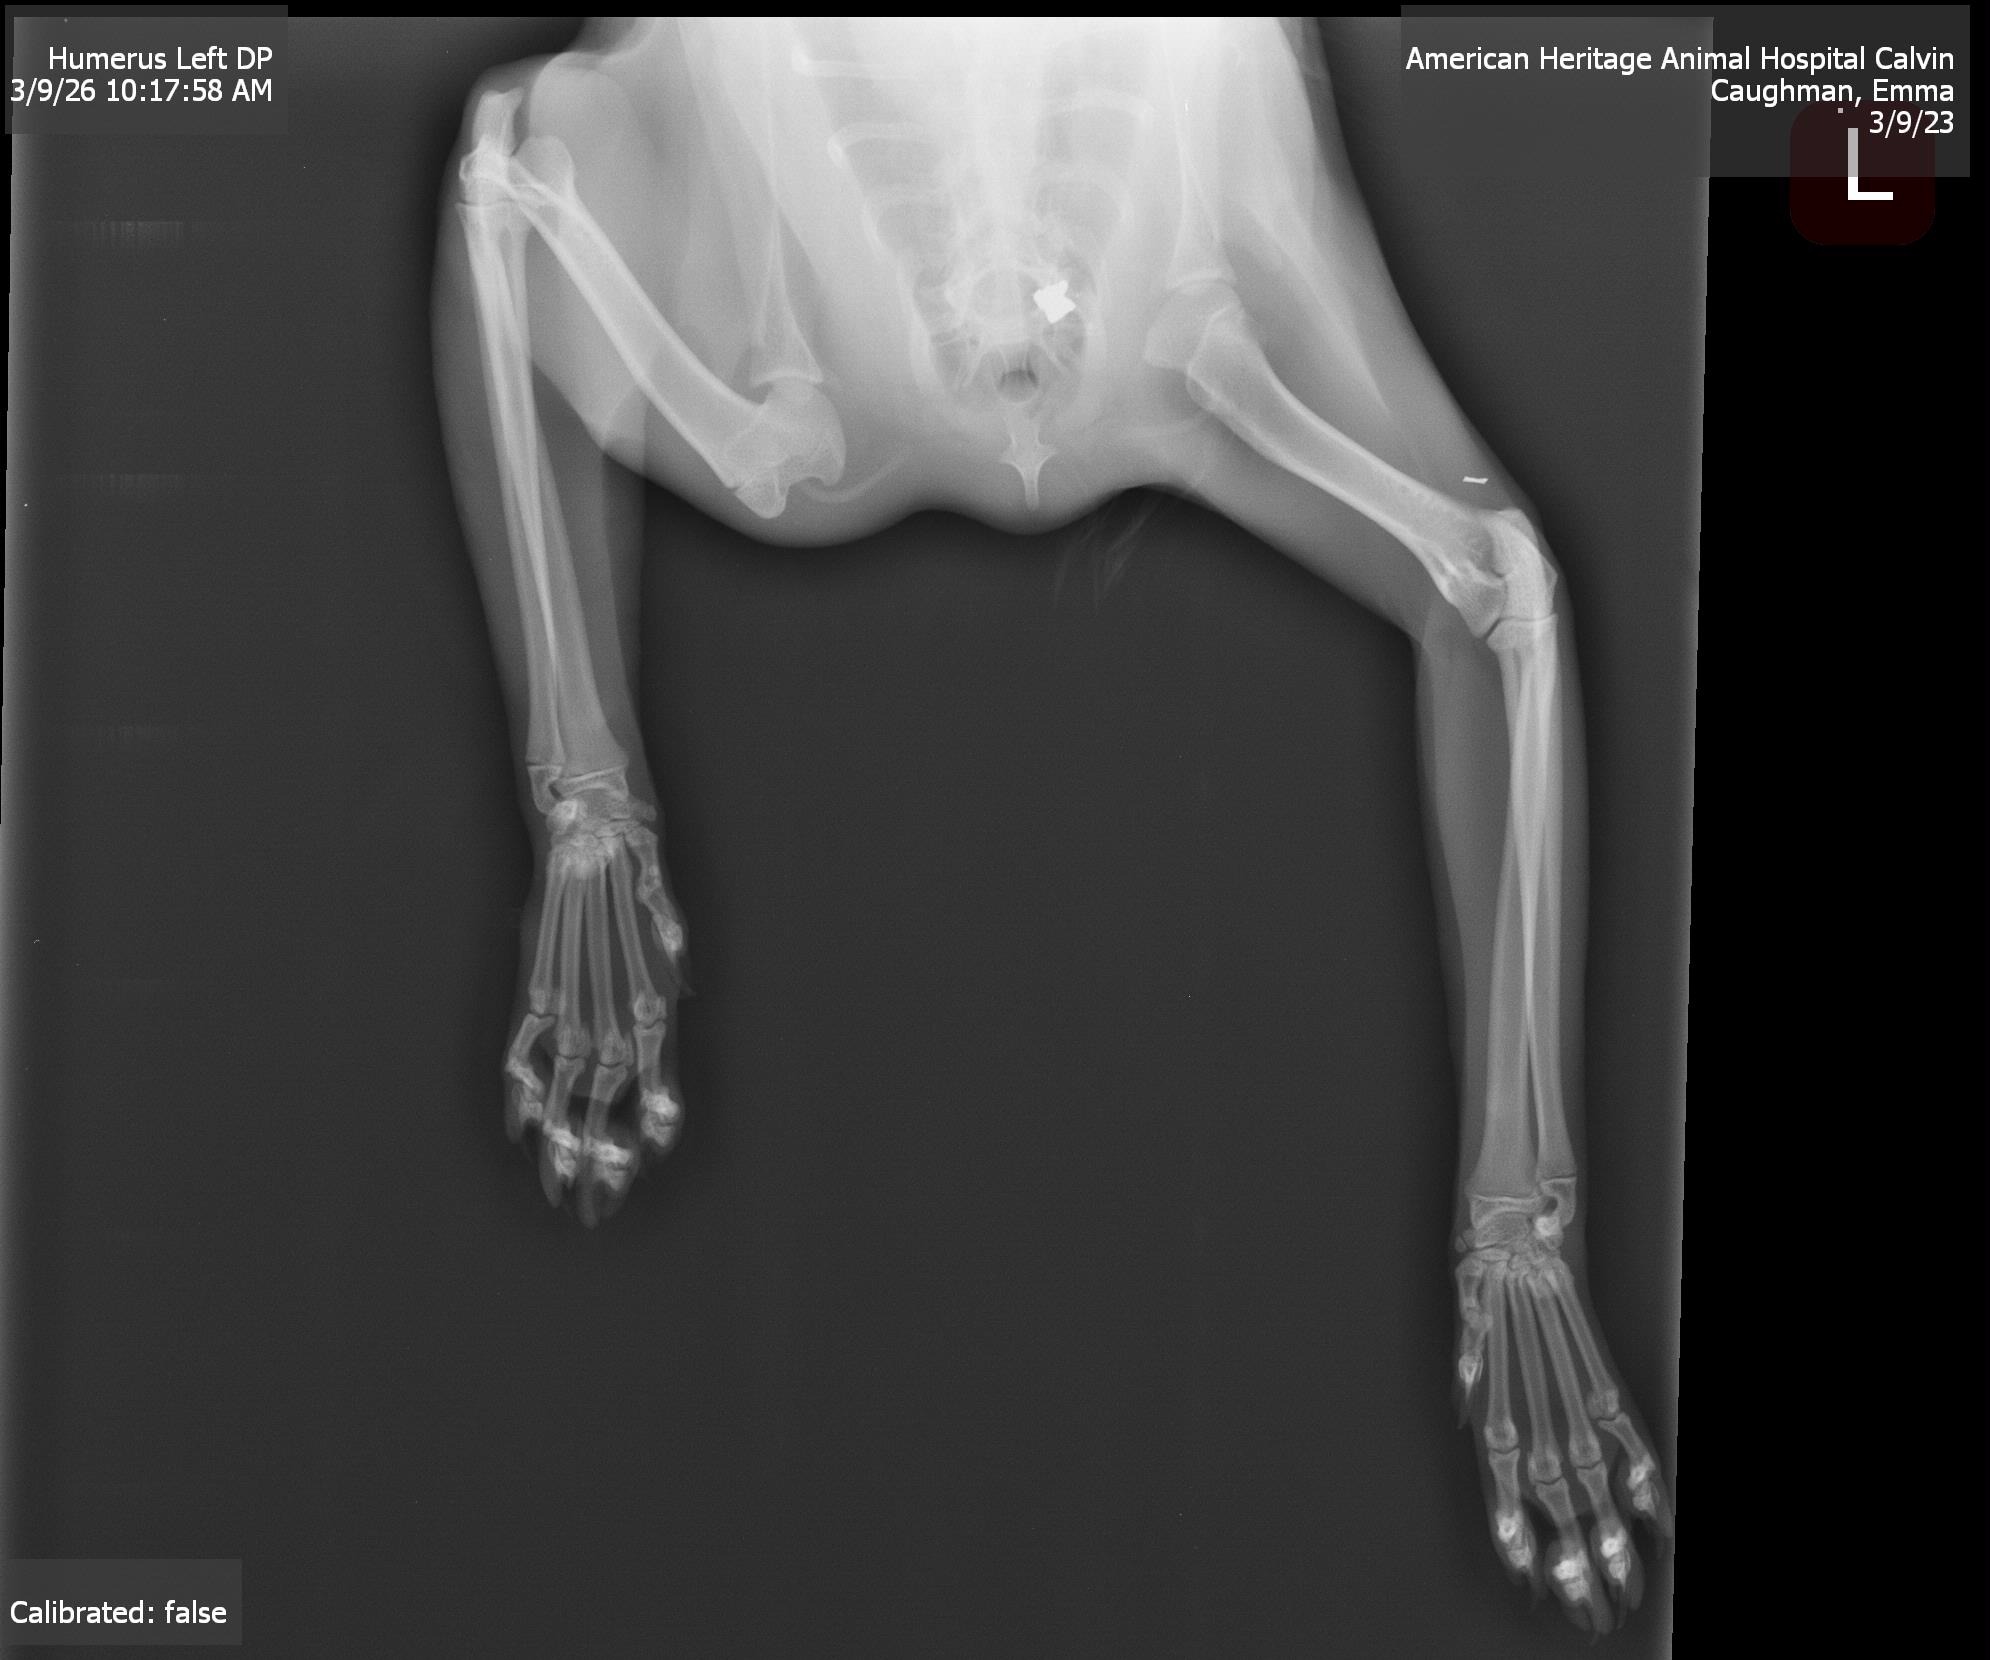

This is Calvin. One of our neighbors shot him. Calvin is one of the neighborhood strays in our community, and we've fed and cared for him since he was a kitten. Since he grew up around us, he's very social and super friendly—honestly, I've never met a cat this sweet. On Friday, we found him crawling up to our door, stumbling and dragging his front leg, with a bloody wound on his neck. We assumed he'd broken his leg and thought he'd been attacked by something or possibly hit by a car. But after taking him to the vet, we learned that what he went through was much, much worse. The vet took an X-ray, which showed a bullet lodged in his spine. The bullet barely missed his artery and is only a hair away from his spinal cord. They believe that it's damaged a nerve that has affected his ability to move and feel his leg. His prognosis is uncertain, as surgery to remove the bullet would cost thousands of dollars, which we don't have. Now, all we can do is wait and see what happens. If the bullet migrates, he could become completely paralyzed and would have to be euthanized. We've already spent a lot in vet bills, and as much as we'd love to get him surgery to remove the bullet, we simply can't afford it. We're trying to raise money to give him the best chance of survival. If he doesn't make it, we will use any funds raised to TNR the remaining community cats. We love Calvin and want to give him the best chance at life. Any support, no matter how small, will make a difference for him and our community cats. Please help us save Calvin and support our neighborhood strays.